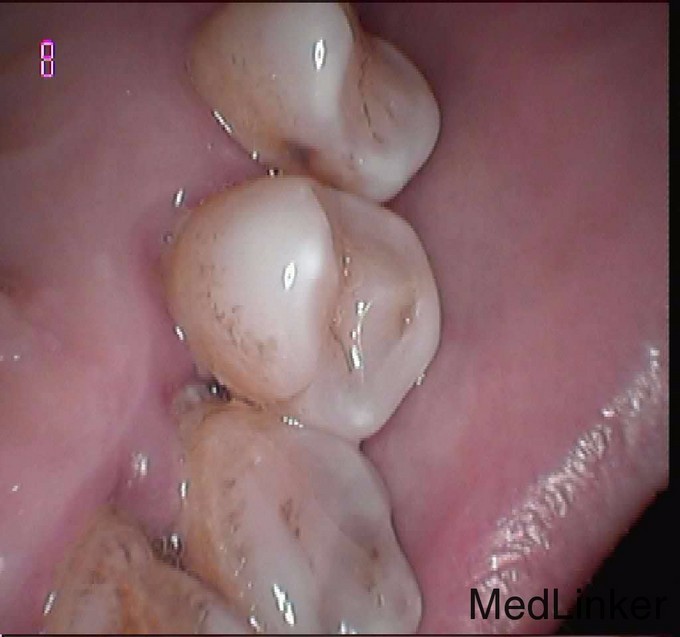

患者,要求治疗,左上56塞牙,冷热刺激痛明显,叩痛,根管治疗后,烤瓷牙冠修复